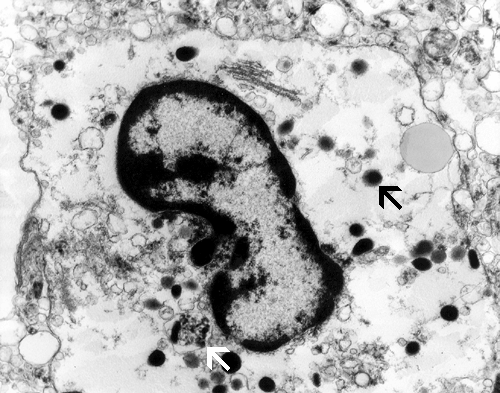

Electron microscopy: On electron microscopy, these cells contain numerous lysosomal vacuoles consistent with active phagocytosis (Arrows in Panel K). The nuclear membrane is rimmed by a layer of chromatin and there is also a large, prominent nucleoli.

Under the electron microscope, the microorganisms in the Vichow-Robin space appear as round cells with many phagocytic or lysosomal vacuoles. A large nuclei with chromatin lined nuclear membrane and large, prominent nucleoli is also helpful in identification.